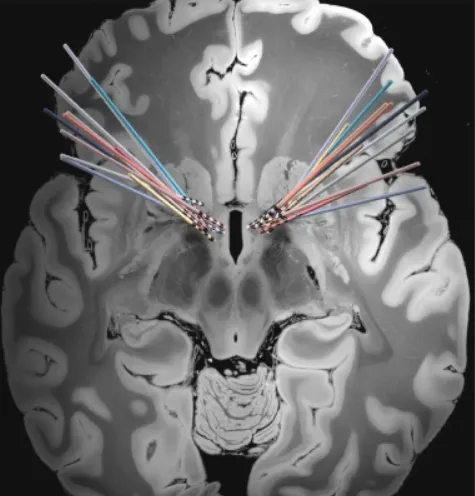

就像起搏器设备如何调节心脏的电活动一样,DBS设备调节大脑的电活动。DBS设备将来自发生器的电脉冲通过一对细导线(导线)传输到大脑的特定目标区域,这些脉冲通常被植入胸腔上部。通过精确调整刺激参数,电脉冲能够促使功能失调的大脑回路逐渐恢复至正常状态。

该团队的目标是了解在theta(4—8赫兹)到alpha(8—12赫兹)范围内的低频大脑震荡是如何在患有严重的,治疗难治性强迫症的个体中发生改变的。大量科学文献发现,theta(4—8赫兹)到alpha(8—12赫兹)范围内的低频大脑震荡在认知过程中发挥着突出作用。为了做到这一点,他们利用了现代DBS设备的一个新功能——不仅能够提供刺激,还能记录大脑活动。